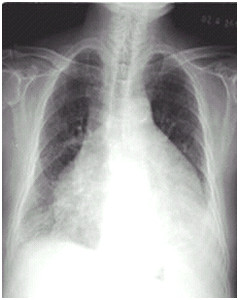

临床助理执业医师实践技能第一站【X线-胸腔积液】知识点模拟题

临床助理医师实践技能第一考站影像诊断模拟试题(2分)